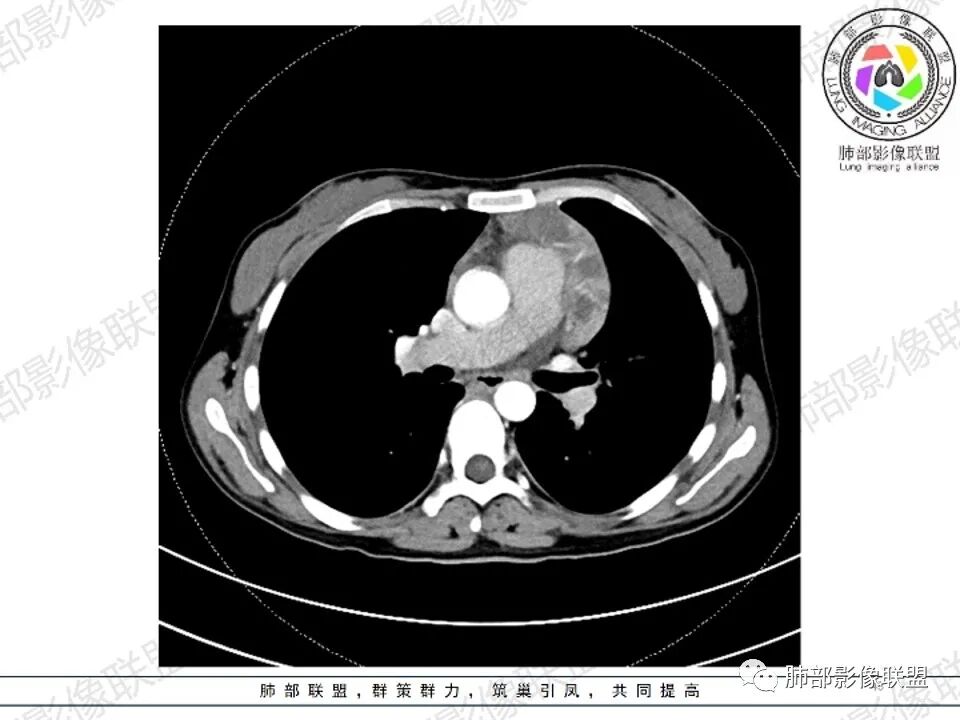

2.影像显示前纵隔不规则块状影,依势贴附心脏大血管旁,密度不均,边界不甚清楚,有结节融合感。

3.病灶轻度不均匀强化,可见血管穿行,散在液性低密度区。

双肺门未见肿大淋巴结。

4.双侧腋窝区见增大淋巴结,边界清楚。